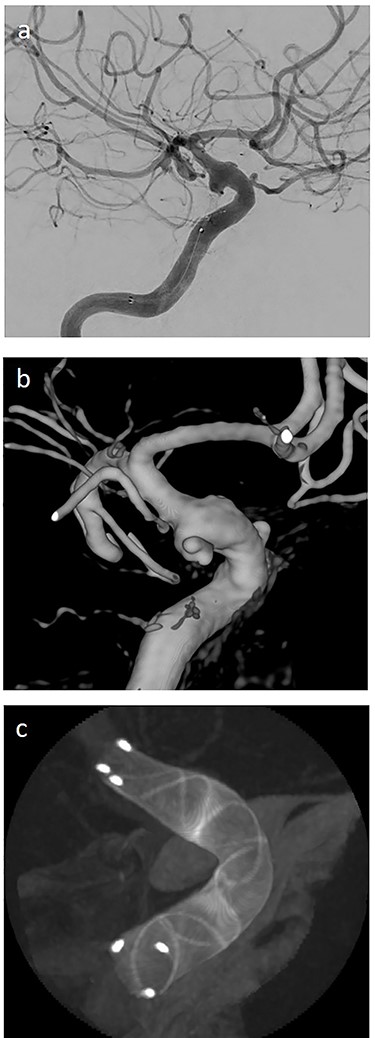

(a) lateral angiogram of left carotid artery showing an ICA aneurysm; (b) 3D reconstruction of the pseudoaneurysm with (c) flow diverter (Derivo®—4,5/20) reconstruction.

On the next day (Day 9 post-op), the patient suffered from acute and devastating headaches, with screaming and enuresis. An emergency computed tomography (CT) was carried out and displayed a prepontine and retroclival subarachnoid hemorrhage (Hunt & Hess Grade I), (Fig. 2). For further evaluation, a digital subtraction angiography (DSA) was conducted, and it showed a pseudoaneurysm of ophthalmic1/supraclinoid2/C23 part of the left ICA, which was directly treated by a flow diverter (Derivo®—4,5/20), with remaining rest flow (Fig. 3). The patient was transferred to the ICU, transcranial doppler sonography was performed and revealed normal flow. In the following course, the patient suffered from Terson’s syndrome and hyponatremia due to SIADH, but after clinical improvement, was transferred back to normal station after 10 days of post-operative monitoring. Furthermore, the patient was plagued with cephalgia and nausea, which could not be compensated with analgetics and antiemetics. On the 20th post-operative day after the epileptic seizure with postictal vigilance reduction, an emergency CTA was conducted showing progressive SAH (Fig. 4) and a growing pseudoaneurysm as well as generalized vasospasm with posthemorrhagic hydrocephalus. For an emergency CSF diversion, an external ventricle drain was placed. The repeated DSA showed a growing false aneurysm which was treated with two additional flow diverters (2× Derivo®—4,5/20) as well as coiling (HydroSoft™ 2/3 and 2× 1,5/2) by endoleak (Fig. 5). The vasospasms were treated by an intraarterial spasmolysis (Fig. 6).